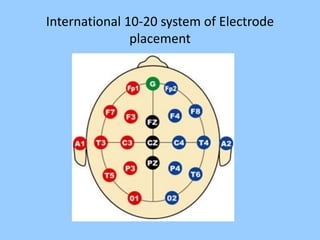

3. International standards for EEG electrode placement and recording parameters are reviewed. Characteristics of different EEG waves, amplitudes, and patterns are described.